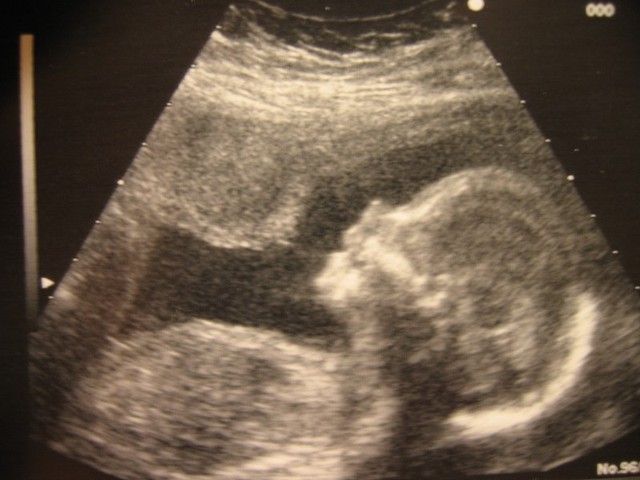

Jakaminen Sulje Sikiön kehitystä voidaan seurata ultraäänikuvauksen avulla. Pysyvä osoite https://peda.net/id/cbb73753deb Pysyvä tiedoston latausosoite https://peda.net/id/cbb73753deb:file/download/99f4da31b57719ae71066ca8874588788cb4efa2/shutterstock_ultra_aani_sikio.jpg Jakaminen muihin palveluihin Share this page to Facebook QR-koodi